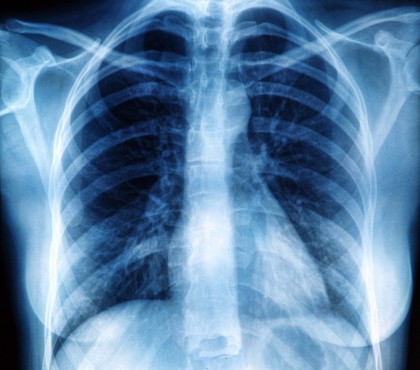

În cercetările publicate recent în Medical Image Analysis, o echipă de ingineri a demonstrat că un algoritm de inteligență artificială pe care l-au dezvoltat, este capabil să prezică rezultatele pacienților cu COVID-19, în mod specific dacă un pacient va avea sau nu nevoie de intervenție în camera de terapie intensivă. Echipa de cercetare, condusă de Pingkun Yan, profesor asistent de inginerie biomedicală la Institutul Politehnic Rensselaer, a combinat datele imagistice de tomografie computerizată toracică (CT) cu date non-imagistice, precum datele demografice, semnele vitale și rezultatele testelor de sânge de laborator, în crearea algoritmului.

Algoritmul a fost testat pe seturi de date colectate de la aproximativ 300 de pacienți din trei spitale diferite, din Statele Unite, Iran și Italia. Cercetătorii au reușit să compare previziunile algoritmului cu ce tip de tratament a fost necesar pentru fiecare pacient, rezultatele fiind unele încurajatoare. Echipa de specialiști speră să transpună algoritmul într-o metodă pe care medicii de la Massachusetts General o vor putea folosi pentru a-și evalua pacienții.

Pe măsură ce echipa își continuă activitatea, algoritmul va putea fi integrat împreună cu un alt algoritm, dezvoltat anterior de aceeași echipă de cercetători, care poate evalua riscul unui pacient cu boli cardiovasculare, utilizând scanări CT toracice. „Știm că un factor cheie în mortalitatea prin COVID este dacă un pacient are afecțiuni subiacente, iar boala cardiacă este o comorbiditate semnificativă”, a spus Yan.